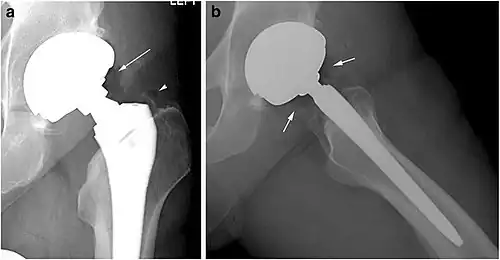

X-ray of a hip with hip replacement and pneumarthrosis, in this case aseptic. -

A vacuum sign, or vacuum phenomenon, is a normal finding on shoulder X-rays.